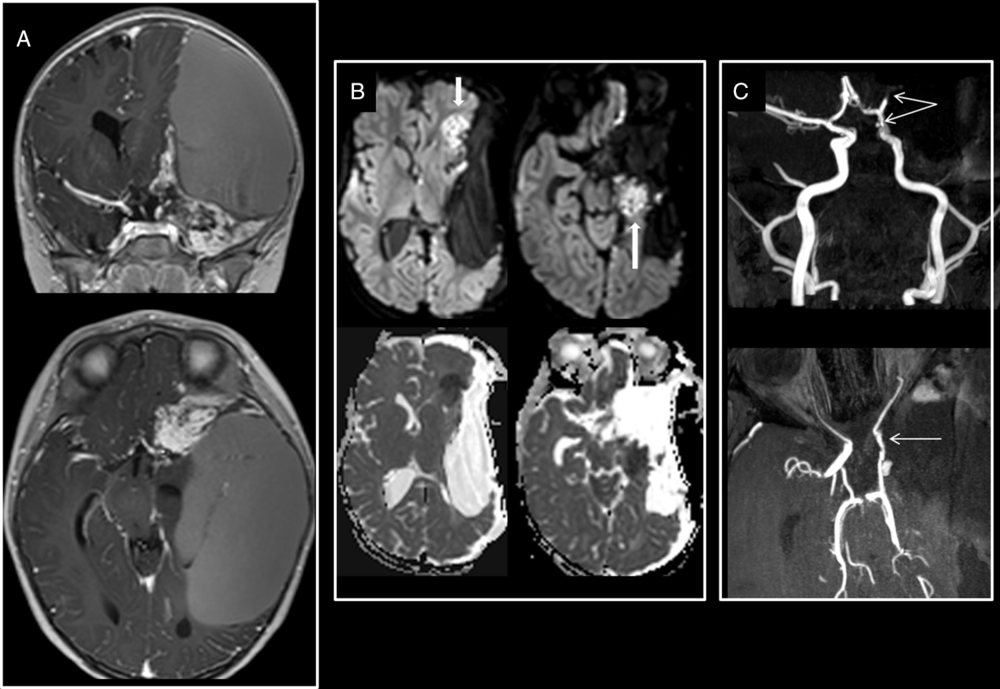

Figure 1: Large craniopharyngioma encasing the right circle of Willis. (A) Preoperative T2-weighted and T1-weighted post-gadolinium administration show a large craniopharyngioma encasing the right ACA, MCA as well as the supraclinoid segment of the right ICA. (B) Intraoperative axial isotrace and ADC maps at the level of the basal ganglia show restricted diffusion from a hyperacute infarct of the posterior limb of the right internal capsule which is irrigated by branches from the right anterior choroidal artery. (C) Early postoperative unenhanced CT and MRI ADC map and isotrace images show the significant progression of the ischemia encompassing both the right ACA and right MCA vascular territories. Postoperative 3D TOF-MRA (C) done on day 11 postsurgery confirmed a persistent narrowing of the right ICA and the absence of flow in the right MCA, both vessels encased but not narrowed on initial diagnostic imaging.